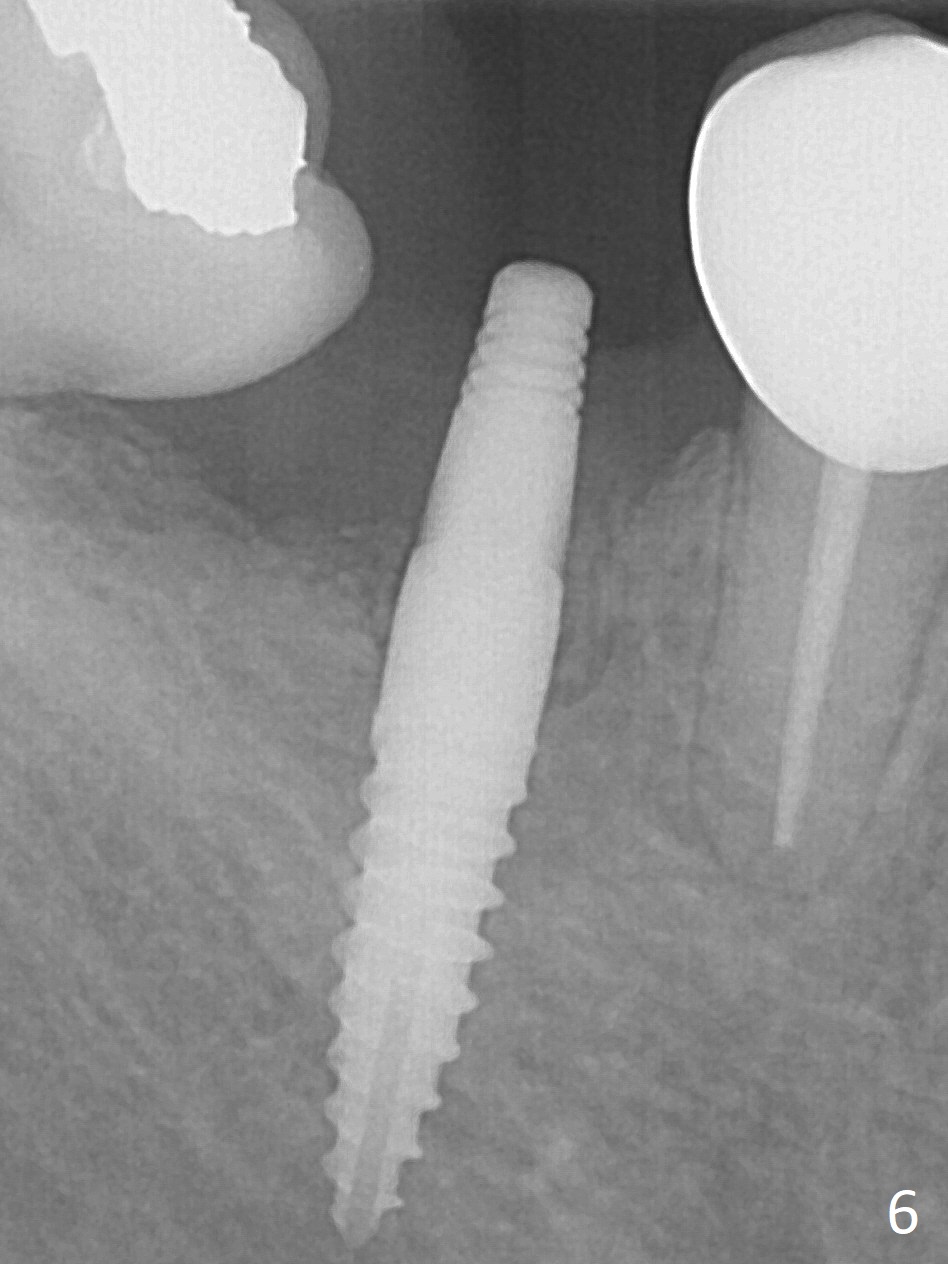

Incision reveals a narrow ridge and a narrow mesiodistal space at #30 (Fig.1). It seems that a 1-piece implant is indicated. Due to limited mouth opening, a 1.2 mm drill is unstable in place after use for 10 mm; instead a 1.5 mm drill is able to be inserted for 8 mm (Fig.2). A 3x10(2) mm 1-piece dummy implant is placed with 40 Ncm at an apparently acceptable level (Fig.3 >). Clinically a few threads are exposed buccally. When a definitive implant with the same dimension is inserted with 45 Ncm, it looks seated too deep (Fig.4,5). The latter is noted after suturing. The implant is backed up for a few turns so that the length of the abutment appears a little more reasonable. Introspectively, a 4 mm cuff should have been used after ridge reduction. Although there is no bone loss 4 months postop (Fig.6), the abutment margin (Fig.7 arrow) is subgingival (red dashed line: gingival margin). Diode laser is used for gingivectomy prior to impression. The bone density around the implant increases 11 months post cementation (Fig.8 *), probably related to recurrent #18 infection. The patient uses floss after meal.